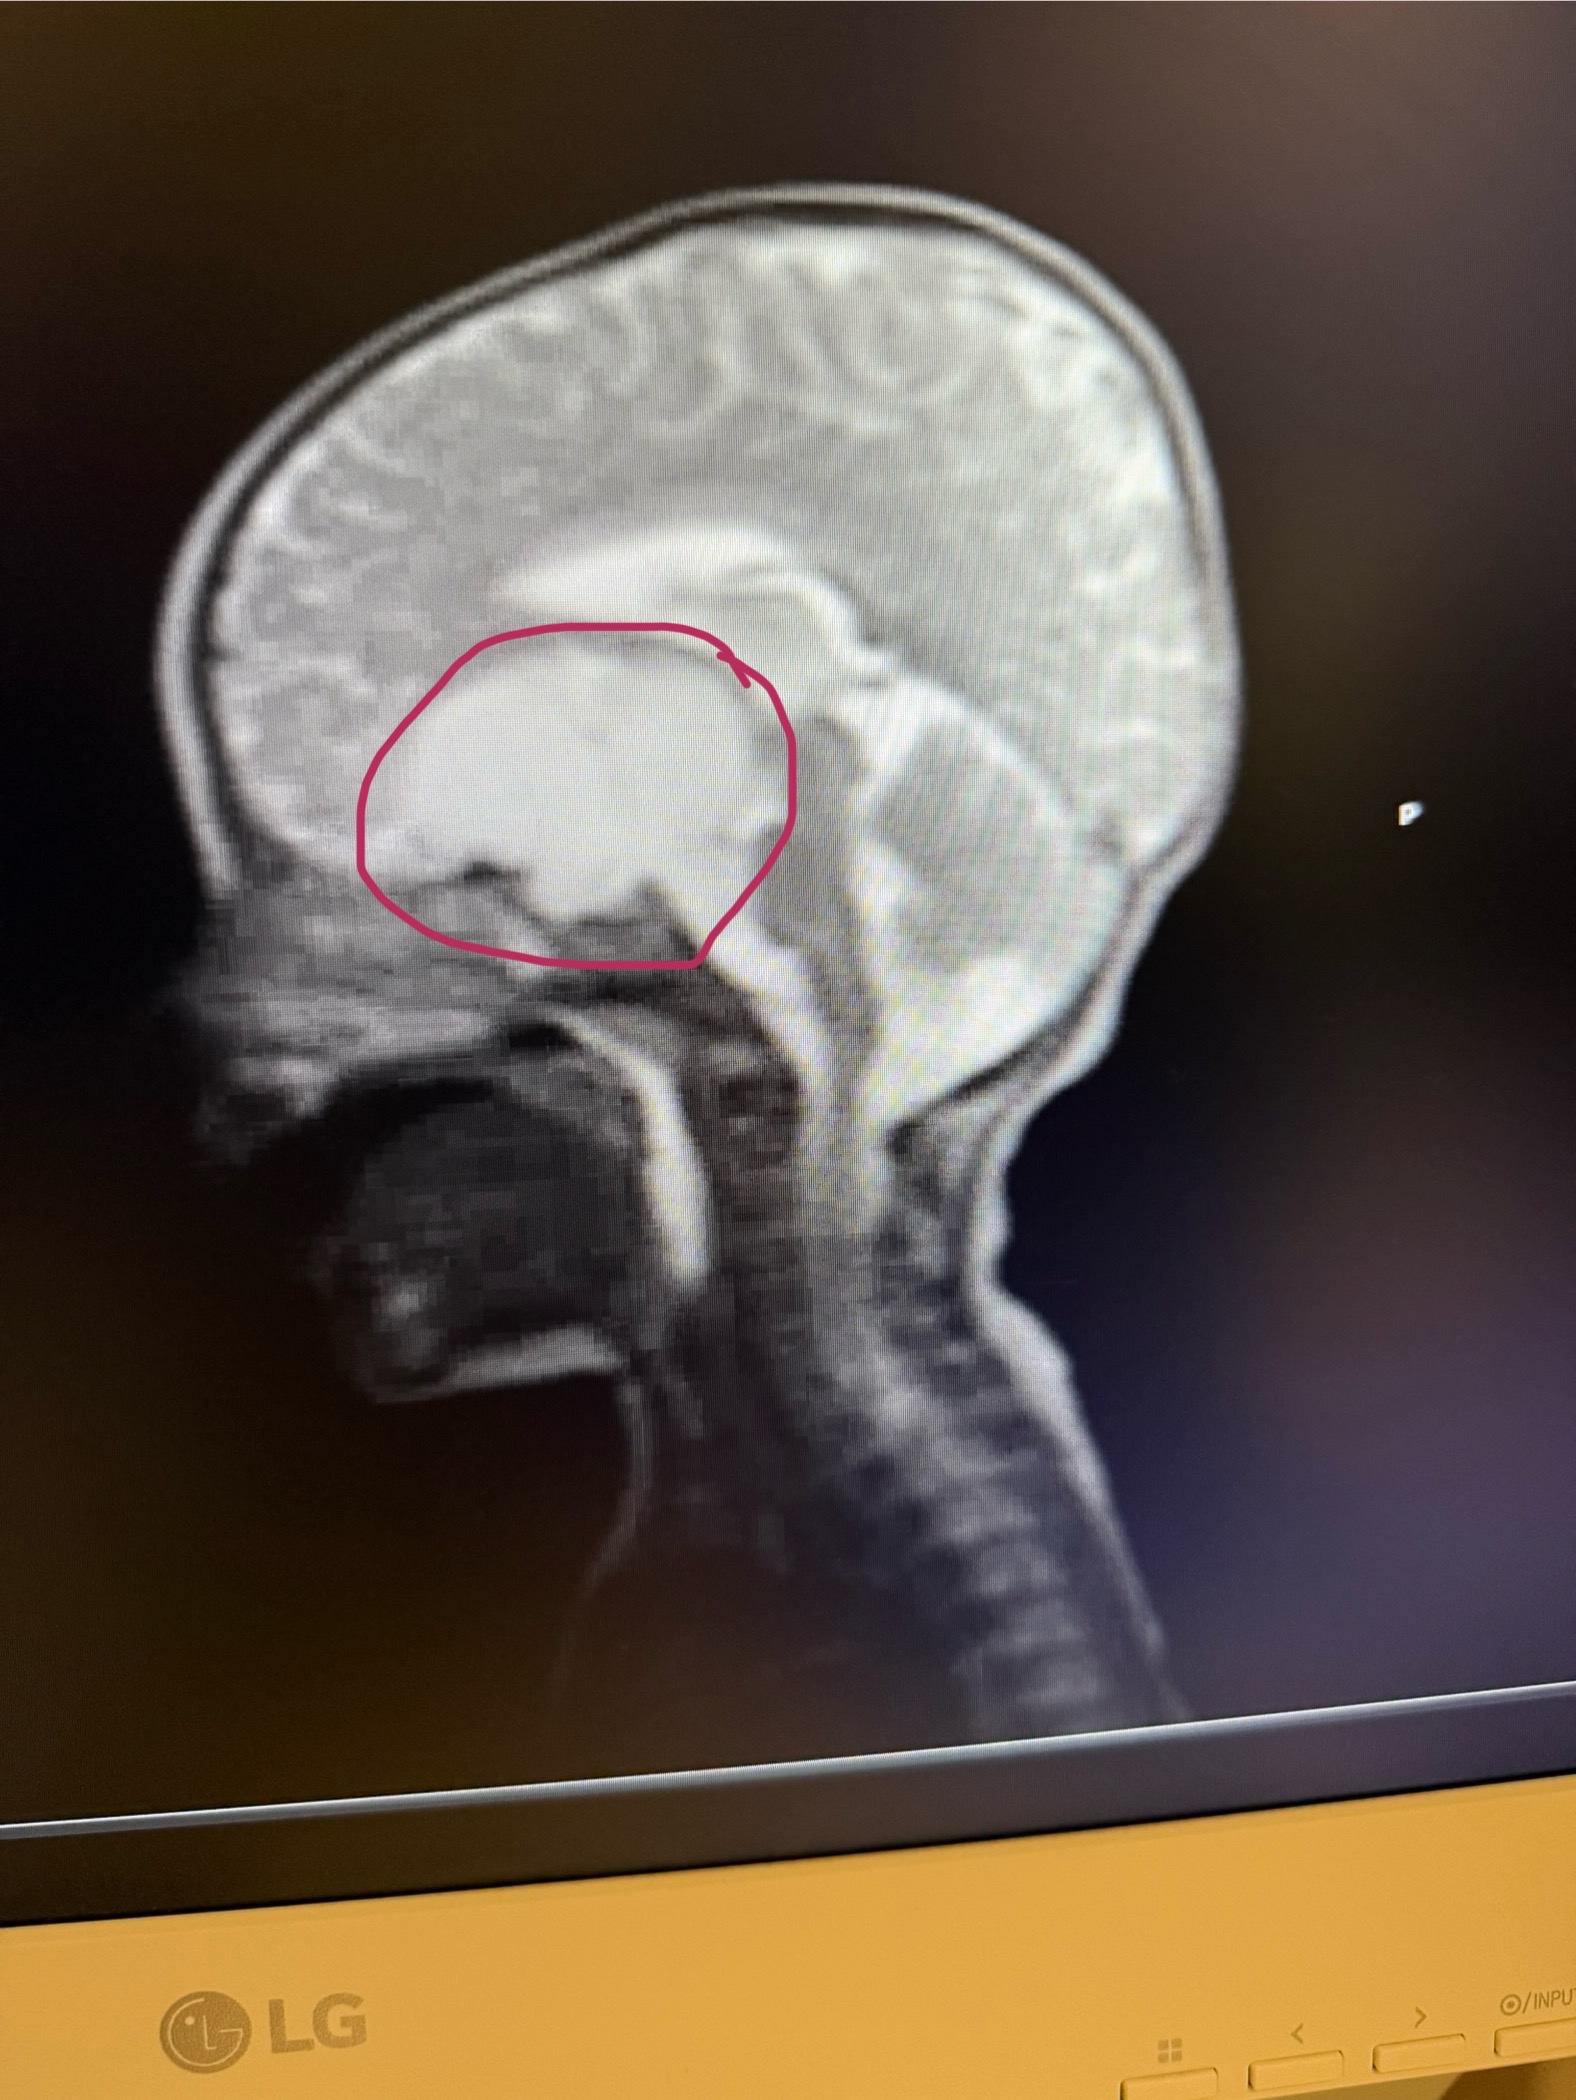

Roy was diagnosed with a brain tumor (Low Grade Glioma) at 9 m of age. We are looking for as much support for this family as possible. His mom has had to leave her job to care for him, so any material donations like diapers (size3) or wipes (PAMPERS BRAND ALLERGY) (SCENT FREE WIPES) would be welcome as well. Thank you and God bless.

April 18th which was Good Friday our world crumbled and found out that our little boy has a brain tumor. We were told that it can not be removed due to it being to close to his eyes and brain stem but a good chunk can be taken out, biopsy will be sent off, and we will get results back in 2-4 weeks. We were set up to have brain surgery the next day but unfortunate events kept happening in the O.R that his surgery happened on EASTER April 20, 2025.

On May 7,2025 Roy had a follow up with oncology and we found out it was cancerous, Low grade Glioma (Pilomyxoid astrocytoma) to be more specific. From what we thought was the plan for him to get outpatient chemo quickly turned into being admitted that Friday due to him refusing to eat what he needed and his diaper output wasn’t where it needed to be. During the hospital visit he has received a gtube (to insure that he gets the nutrition his little body needs) and a picc line (for easy access to drawing labs and giving chemo/other meds).